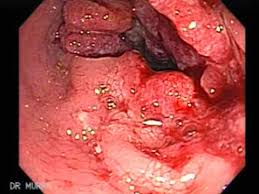

Even after seeking medical attention, patients are still often misdiagnosed with having hemorrhoids. Rectal and colon cancer are. Cancer can coexist with benign. Hemorrhoids, also called as piles, are dilated rectal veins. A diminutive rectal polyp amidst internal hemorrhoids, detected by rectal retroflexion during colonoscopy, was shown to harbor invasive rectal adenocarcinoma by colonoscopic biopsy. The other sign is a lump near the anus, which is similar to hemorrhoids. Three years later she died. Most common signs or symptoms that both rectal cancer and hemorrhoids are bleeding from the rectum, more gas, stool size, and diarrhea. Because the symptoms of hemorrhoids and the early stages of rectal cancer are similar, and can be easily confused or misdiagnosed, we recommend early examinations for accurate detection. However, there are significant differences in how the two conditions manifest. Internal hemorrhoids are most commonly associated with a potential colon cancer misdiagnosis. Colorectal cancer may be mistaken for inflammatory bowel diseases (ibds) such as irritable bowel syndrome (ibs) and ulcerative colitis. K for the rest of his life—a case that would cause the premature retirement of his supervising physician.

Initially this lesion had appeared to be a relatively innocuous prominent anorectal mucosal fold and was recognized as … Being able to distinguish between the two can be the difference between uncomfortable bowel motions and something more serious. Early detection means early treatment. Colon cancer (also known as colorectal cancer) is a malignant tumor, arising from the inner wall of the large intestine. Signs and symptom of colon cancer (when they do occur) that do not occur with hemorrhoids may include:

Colorectal cancer misdiagnosed as hemorrhoids it was a case that would haunt mr. Being able to distinguish between the two can be the difference between uncomfortable bowel motions and something more serious. The symptoms of hemorrhoids (also called piles) and bowel cancer can be quite similar but do not have the same fatal results. However, there are significant differences in how the two conditions manifest. A diminutive rectal polyp amidst internal hemorrhoids, detected by rectal retroflexion during colonoscopy, was shown to harbor invasive rectal adenocarcinoma by colonoscopic biopsy. Because colorectal cancer and hemorrhoids are common among americans and they have similar symptoms in early stages, they can be mistaken for one another or misdiagnosed. Pancreatic cancer often causes symptoms in the patient's digestive tract. Colon cancer (also known as colorectal cancer) is a malignant tumor, arising from the inner wall of the large intestine. There is a high incidence of hemorrhoids in the north american population, making them a common condition. Signs and symptom of colon cancer (when they do occur) that do not occur with hemorrhoids may include: Therefore, proper diagnosis is critical. Colorectal cancer can seem a lot like some common gastrointestinal (gi) disorders, including hemorrhoids, irritable bowel syndrome , an infection, or inflammatory bowel diseases , such as crohn. This can lead to misdiagnosis as.